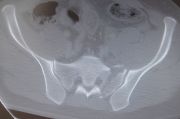

1. Pelvic fracture involved sacrum caused by lateral compression in a 25-year-old male.

Treatment: Percutaneous fixation with two sacroiliac screws

I. Before surgery, axial view of CT scan showing fracture of sacrum on the left side II. Post-surgery, anteroposterior x-ray of pelvis with the two sacroiliac screws